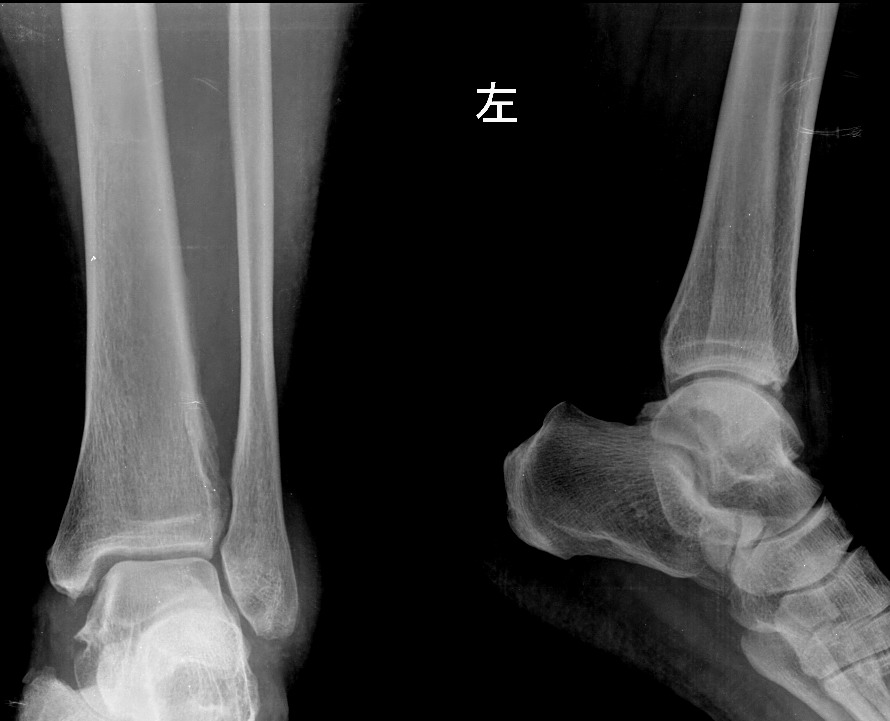

大家帮忙看下左胫骨下段外侧是骨膜反应还是骨间膜改变,或者其它病变

例2、男,52岁,偶有左下肢隐痛,这例腓骨也有异常

例1正常;例2感觉不对,是否为软组织病变所致?不解!

例2考虑骨膜反应。

不是人人有,有了也不见得全是异常。第一例可能是骨间膜改变; 第二例可考虑筋膜慢性炎性浸润所致。

第一例考虑骨间膜,第二例考虑骨膜反应